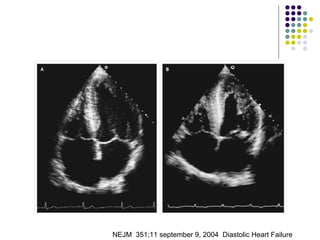

NEJM  351;11 september 9, 2004  Diastolic Heart Failure

Diastolic and systolic NEJM  351;11 september 9, 2004  Diastolic Heart Failure